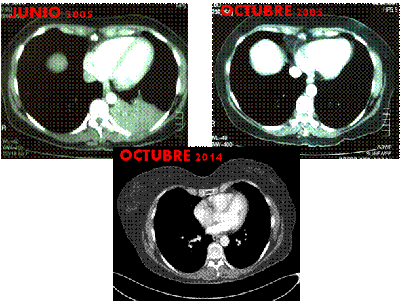

FIGURA 1: Comparativa de TC de tórax con contraste de junio de 2005, octubre 2005 y octubre de 2014 donde se objetiva una masa pulmonar paramediastínica en lóbulo inferior izquierdo (LII) y la desaparición de la misma tras el tratamiento y respuesta mantenida 9 años después.